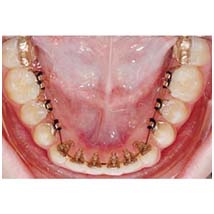

Orthodontic Treatment

- Mal alignment of the teeth are the primary concern of people these days primarily because of the esthetic look.

- This treatment helps to align all the teeth in a proper position.

- This takes care of your functional as well as your esthetic concerns.

- It is performed using brackets and braces.

- Metal -25,000

- Ceramic -35,000

- High end ceramic-45,000

- Lingual -99,000

- Invisible bracketless system -1,50,000-2,00,000